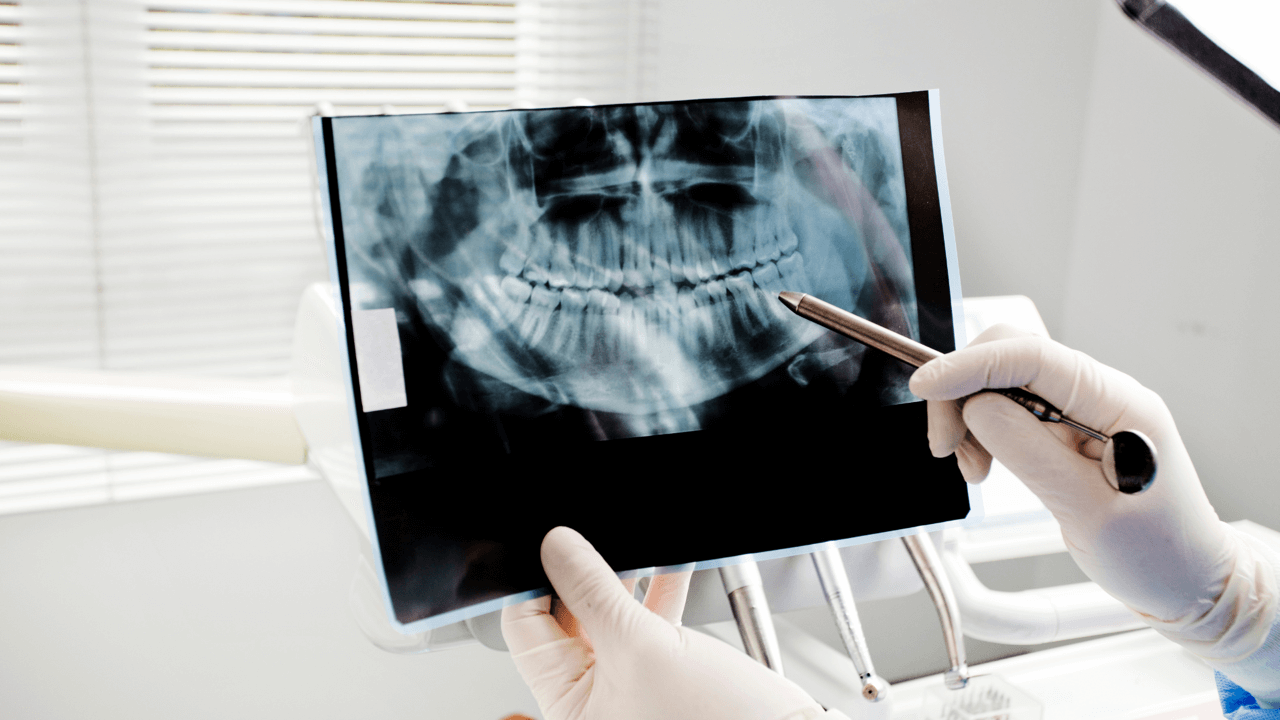

Przygotowanie do zabiegu ortognatycznego trwa około dwóch lat. W przeciągu tego czasu lekarzem prowadzącym jest specjalista ortodoncji. W chirurgii ortognatycznej na szczególną uwagę zasługuje etap planowania, dzięki któremu ostateczny efekt zabiegu staje się w dużym stopniu przewidywalny dla ortodonty oraz chirurga. Na tym etapie wykonywana jest pełna diagnostyka, dokumentacja fotograficzna, wykonywane są konsultacje specjalistyczne oraz niezbędne badania. Warto żeby w okresie przygotowawczym do zabiegu zwrócić uwagę na współpracę z fizjoterapeutą, logopedą oraz psychologiem.